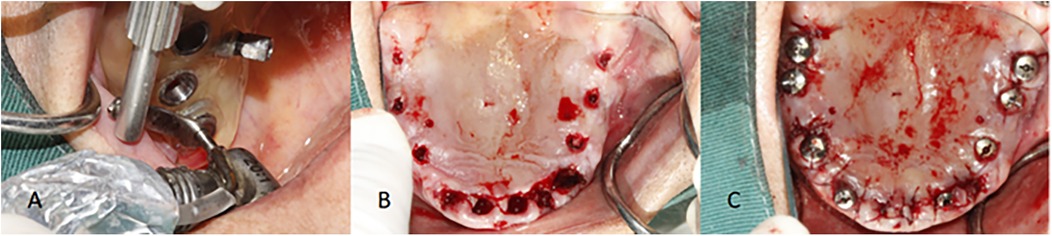

Background: Digital guided implantology improves safety and precision compared to freehand methods. A survey indicated that half-guided templates are more commonly used than full-guided ones in China. This study aims to assess the accuracy of implant placements using half-guided and full-guided digital surgical templates, considering factors like jaw location, tooth position, support type, implant timing, and bone density. Methods: 87 implants (52 half-guided, 35 full-guided) were evaluated by comparing pre-and postoperative CBCT scans to measure deviations in coronal, apical, depth, and angular positions. Bone density was also assessed in relation to the implant deviations. Results: The findings revealed that the half-guided group exhibited significantly greater deviations in several areas: maxillary angular deviations, anterior coronal and depth deviations, posterior depth deviations, tooth-supported guide depth deviations, immediate implant coronal and angular deviations, and delayed implant depth deviations (P < 0.05). No significant differences were noted in other measurements. In the bone density analysis, only the full-guided group showed a significant negative correlation between bone density and apical deviation (P < 0.05). Conclusion: Based on statistical results, power calculations, and subgroup effect sizes, the following clinical recommendations are derived: Half-guided templates, owing to their superior cost-effectiveness in fabrication time and cost, are recommended for use in mandibular posterior regions, mucosa-supported templates, delayed implantations, and clinical scenarios with uneven bone density distribution at implant sites. In contrast, full-guided templates are more suitable for maxillary implantations, anterior regions, tooth-supported templates, immediate implantations, and sites with homogeneous bone density distribution.